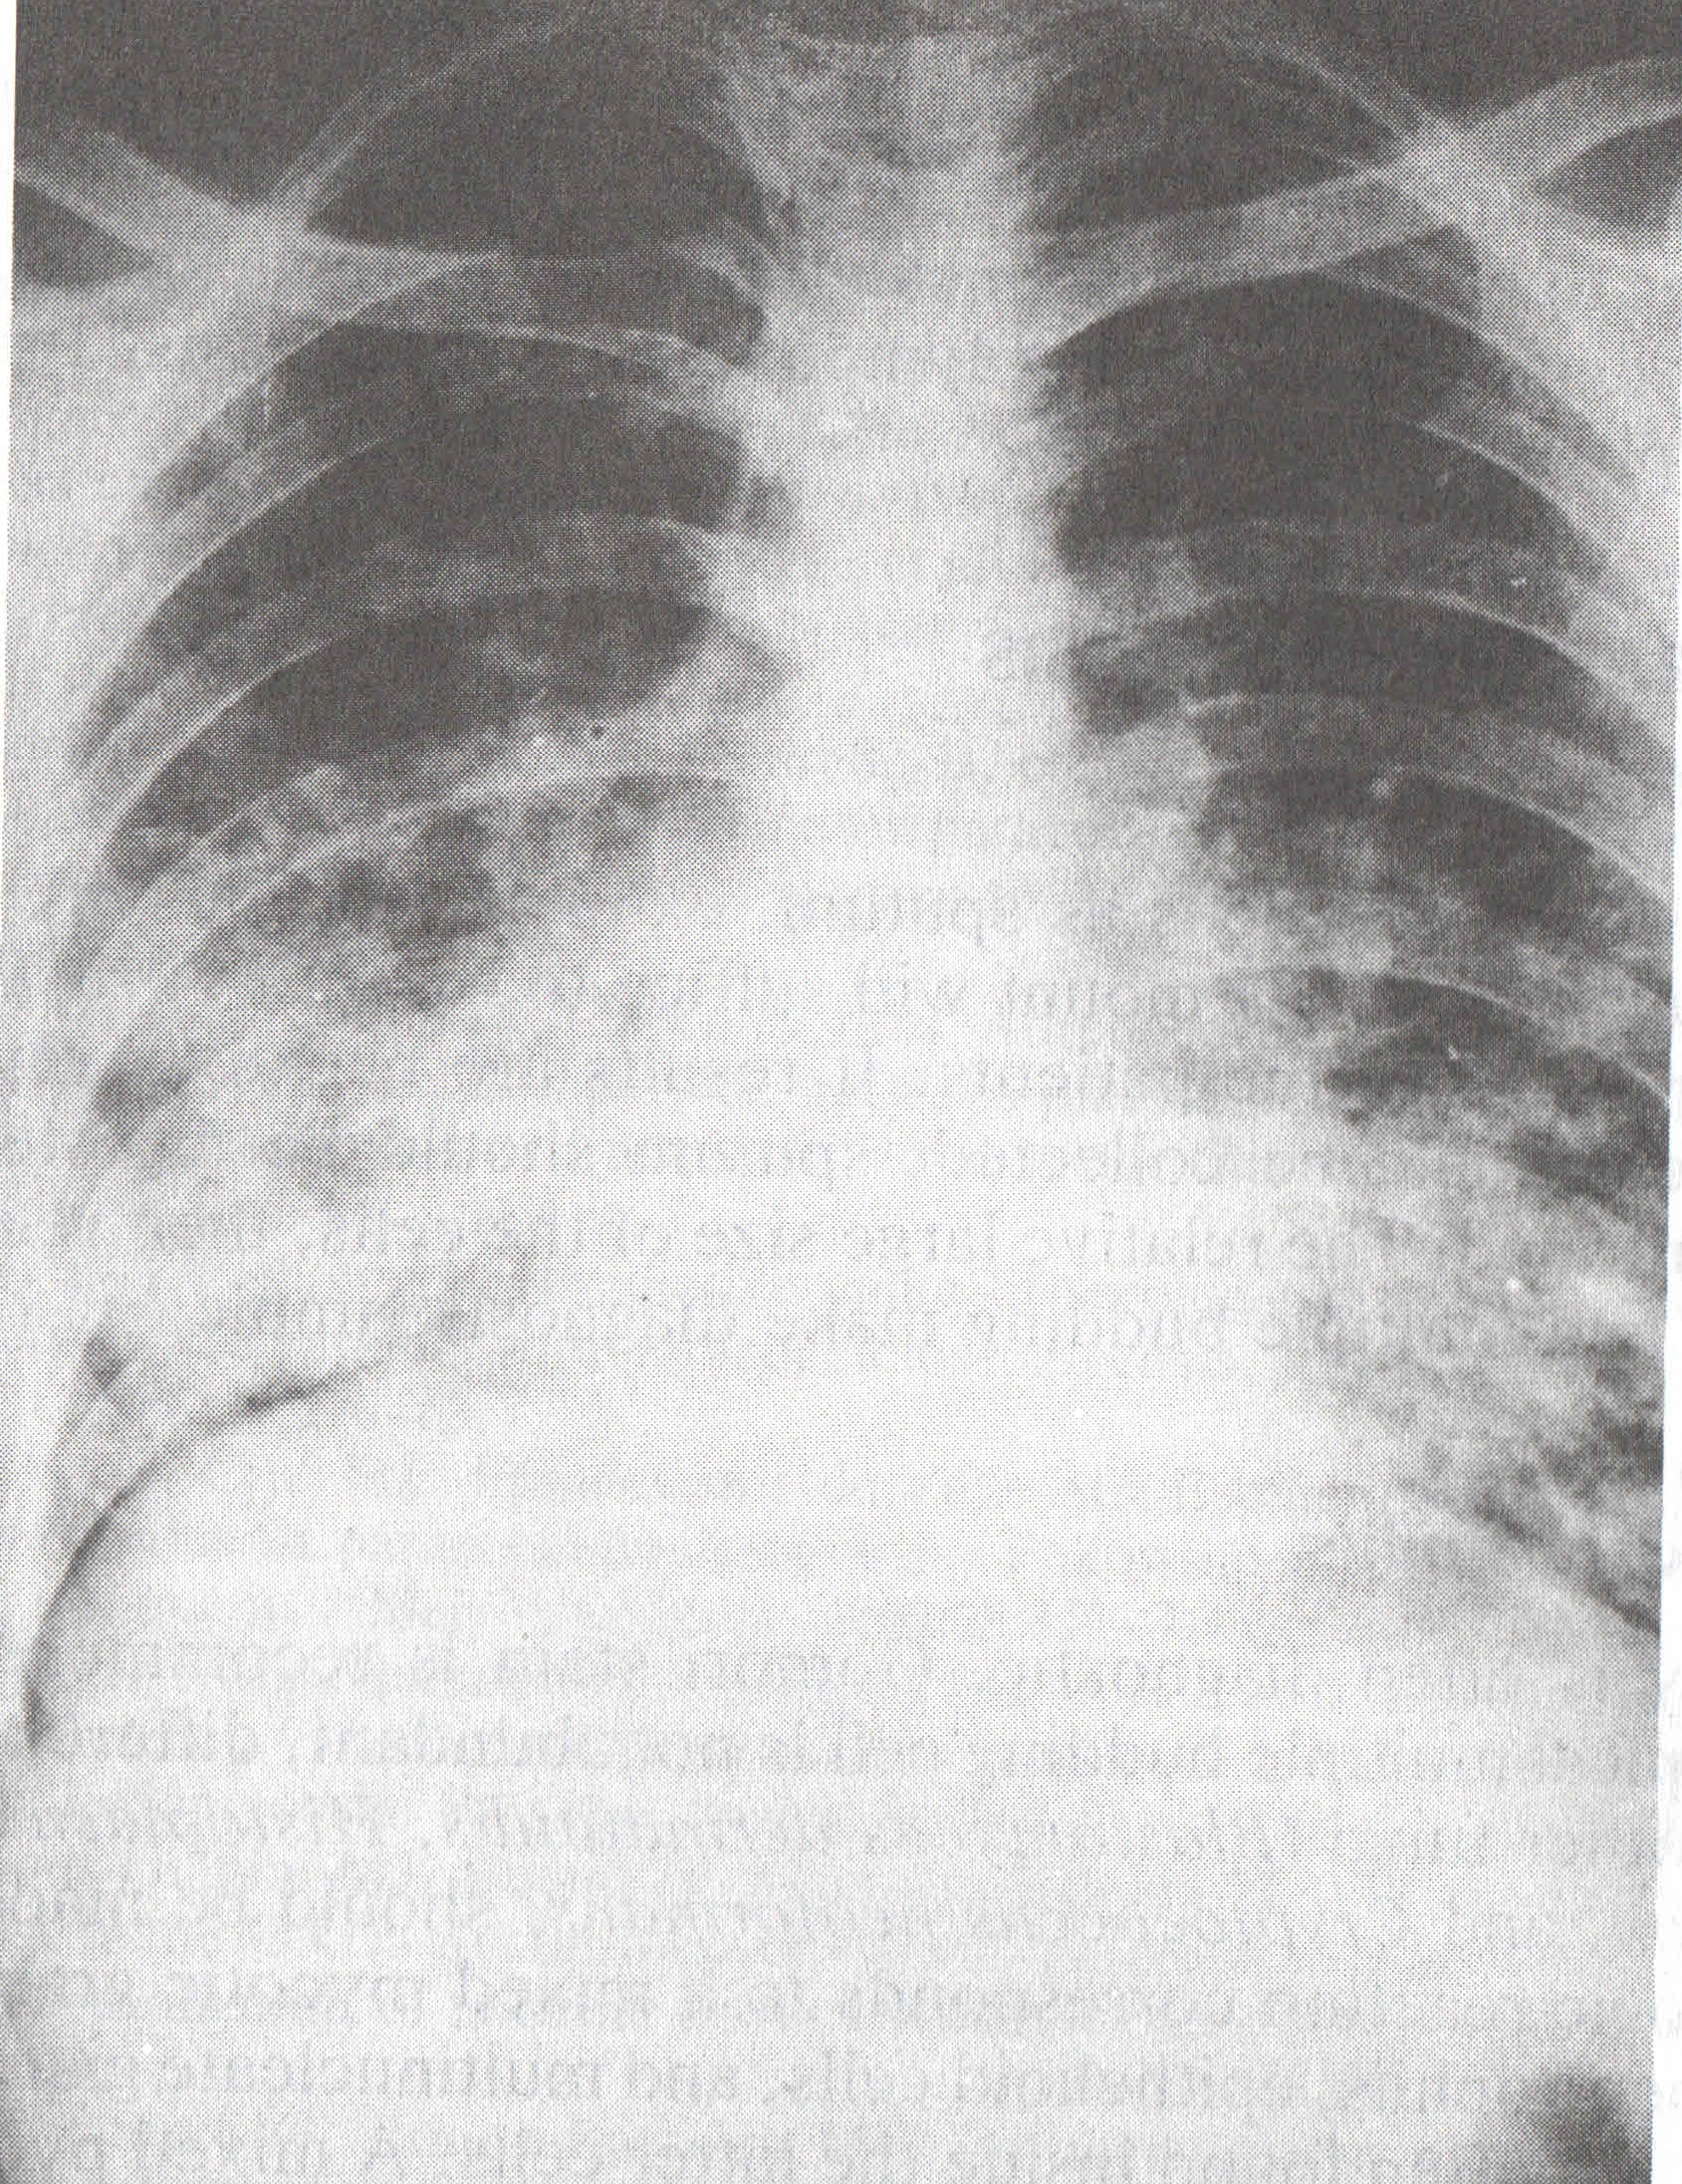

Bu etkenlerin tanısı, mikrobiyoloji laboratuvarı ve hekim için her zaman büyük güçlük oluşturmaktadır. Radyolojik olarak, sistemik fungusların oluşturduğu lezyonları, Candida hariç olmak üzere, Tüberküloz gibi diğer infeksiyoz lezyonlardan ve neoplazmlardan ayırmak oldukça güçtür. Semptomlar sıklıkla tipik olmayıp, pnömonileri, sarkoidozu, kanserleri veya diğer hastalıkları taklit edebilmektedirler. Tekrarlayan durumlarda bile, fungal etkenleri kültürle veya histopatolojiyle ortaya koymak güçtür. Candida ve Aspergillus hariç, üreme çok yavaştır ve 2-6 haftalık zaman almaktadır. Bu nedenle, tedaviye yön vermede seroloji önemli yer tutmaktadır.

HISTOPLASMOSIS M antijenine karşı daha erken, H antijenine karşı daha sonra antikor yanıtı oluşmaktadır. Pulmoner histoplasmosiste M yanıtı daha öndedir. Olguların % 85-94’ ünde serolojik yanıt vardır. Antikor titreleri tanıya yardımcıdır. Histoplasma capsulatum, en sıklıkla görülen tipidir. BOS’ ta pozitiflik, meningeal histoplasmosisi düşündürür. |